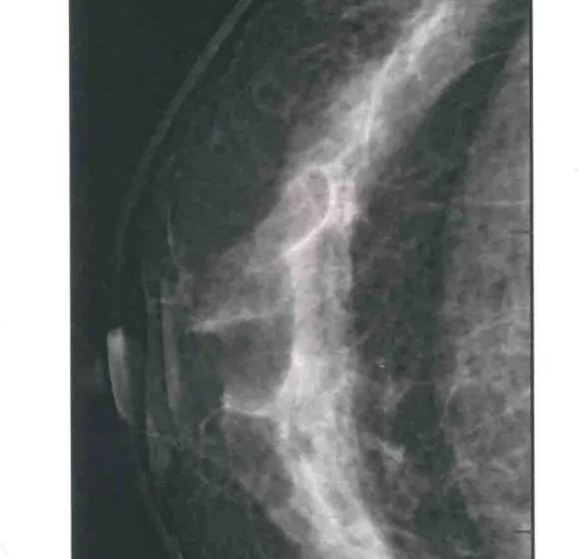

乳腺DR頭尾位/CC位檢查方法

二、圖像顯示要求,含乳腺的基底部及內外側乳腺組織,需要顯示胸肌前緣或胸壁。頭尾位與內外斜位乳頭後線長度差≤1厘米;顯示實質後的乳腺組織,乳頭位於切線位,乳腺組織重疊;雙側乳腺頭尾位照片相對放置,則兩側乳腺呈球形;影像密度和對比度良好,能顯示0.1毫米細小鈣化,清晰沒有偽影異物、運動偽影和切割偽影等。